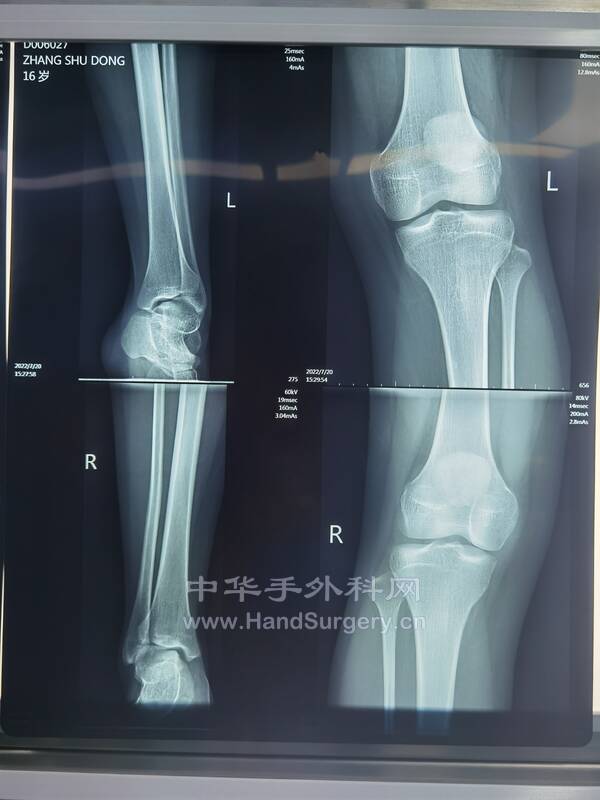

右跟距骨桥,拇外翻术后8周患者复查